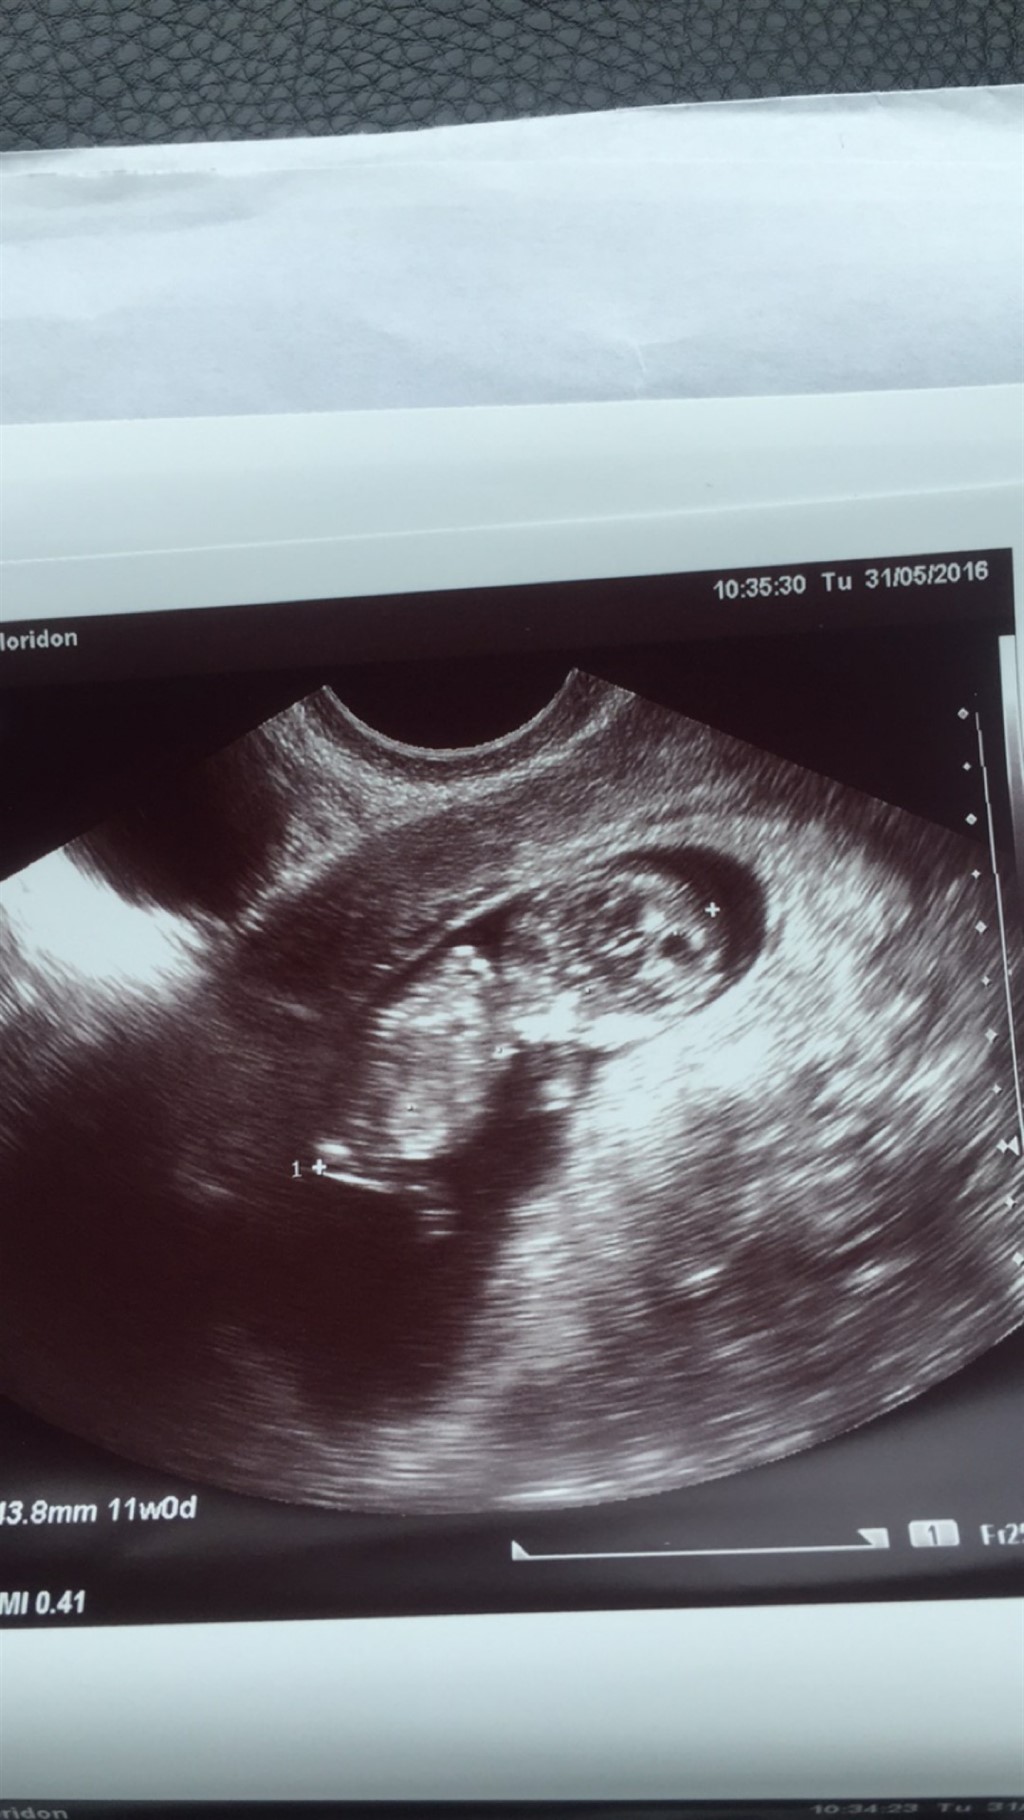

Blev scannet igår , bare sådan en ekstra hygge scanning . En dejlig livlig baby der hoppede og sparkede rundt .

Er 11 + 1 idag . Kan i måske se om det er en dreng eller pige

ved godt det er tidligt men bare for sjov hihi